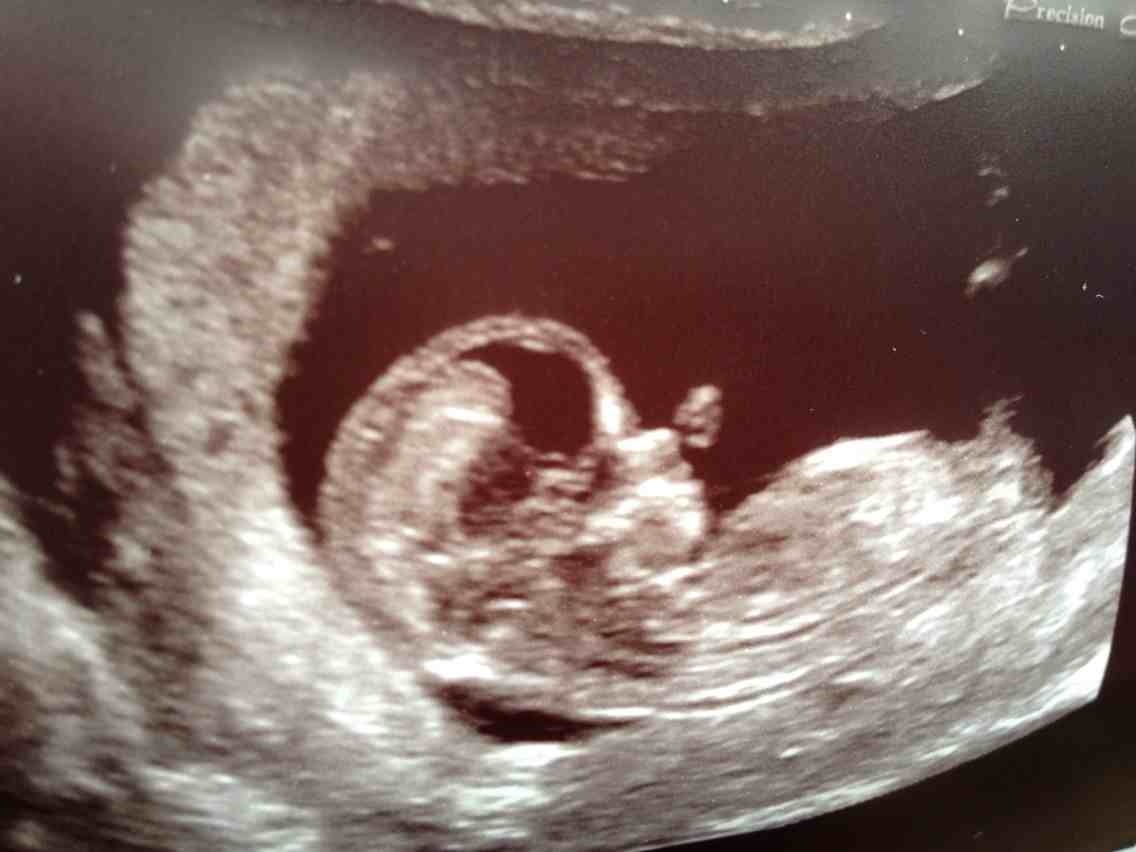

It's hard to tell if that is the nub there or not I am leaning boy but now 100%

Thank you , I think it looks boyish too. Any more guesses? :-)

Boy

Looks boyish. :)